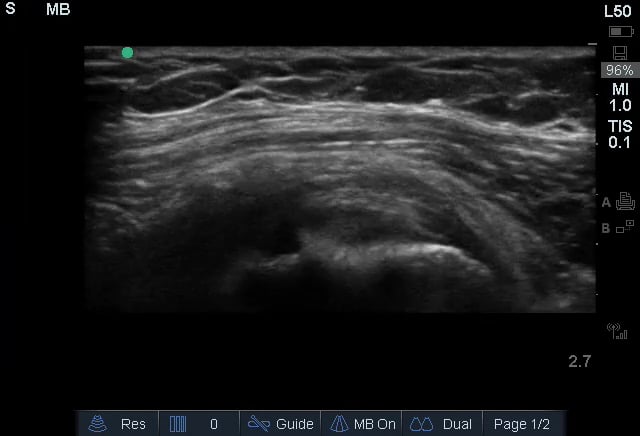

A rotator cuff tear is a common musculoskeletal (MSK) injury involving one or more of the four tendons surrounding the shoulder joint. These tears can range from partial to full-thickness and are a significant cause of shoulder pain and weakness, often resulting from acute trauma or chronic degeneration. In medical imaging, ultrasound is a valuable tool for diagnosing rotator cuff tears due to its real-time capabilities and ability to visualize soft tissue structures.

Ultrasound allows for dynamic assessment of the rotator cuff, identifying fluid collections, tendon retraction, and changes in echotexture that indicate a tear. Early and accurate diagnosis via ultrasound guides treatment decisions, from conservative management to surgical repair, improving patient outcomes and aiding rehabilitation in MSK practice.